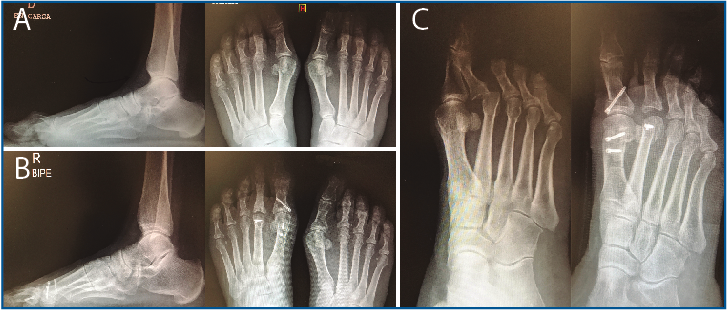

5. Pasamos las suturas por la placa plantar con ayuda de una pinza Mini-Scorpion DX® (Arthrex) (Figura 7) o de un Micro SutureLasso® (Arthrex) (Figura 8). Existen diferentes técnicas según el tipo de rotura. Para la reinserción utilizamos 2 suturas no reabsorbibles de Fiber-Wire® n.º 0 en “doble hilera” proximal y distal (Figura 9). Decidimos una u otra configuración in situ según el tipo de rotura.

Figura 7. Pase de suturas mediante pinza Mini-Scorpion®.

Figura 8. Pase de suturas con ayuda de Micro SutureLasso®.

Figura 9. Disposición de las suturas con técnica de “doble hilera”.

6. Retiramos el distractor y la agK de la falange, y realizamos 2 pequeños túneles de dorsal a plantar en la base de F1 con una broca o agK de 1,2 mm (Figura 10). Estos pueden disponerse cruzados o en paralelo. Aunque la disposición paralela pudiera teóricamente debilitar la base de F1 al ser prácticamente subcondrales, realizarlos cruzados tiene la desventaja de poder interferirse en el pase de las suturas. A través de estos túneles recuperamos las suturas preparadas en el extremo distal de la placa, de plantar a dorsal (Figura 11 y Vídeo).

7. Fijamos la osteotomía de Weil con el acortamiento metatarsal deseado y previamente establecido (se recomienda un acortamiento mínimo de 2-3 mm) (Figura 12). Con la articulación MTF perfectamente reducida y el dedo en 30° de flexión plantar, tensamos las suturas recuperadas en el dorso de F1, hasta llevar firmemente la placa plantar a su base, y anudamos (Figura 13).